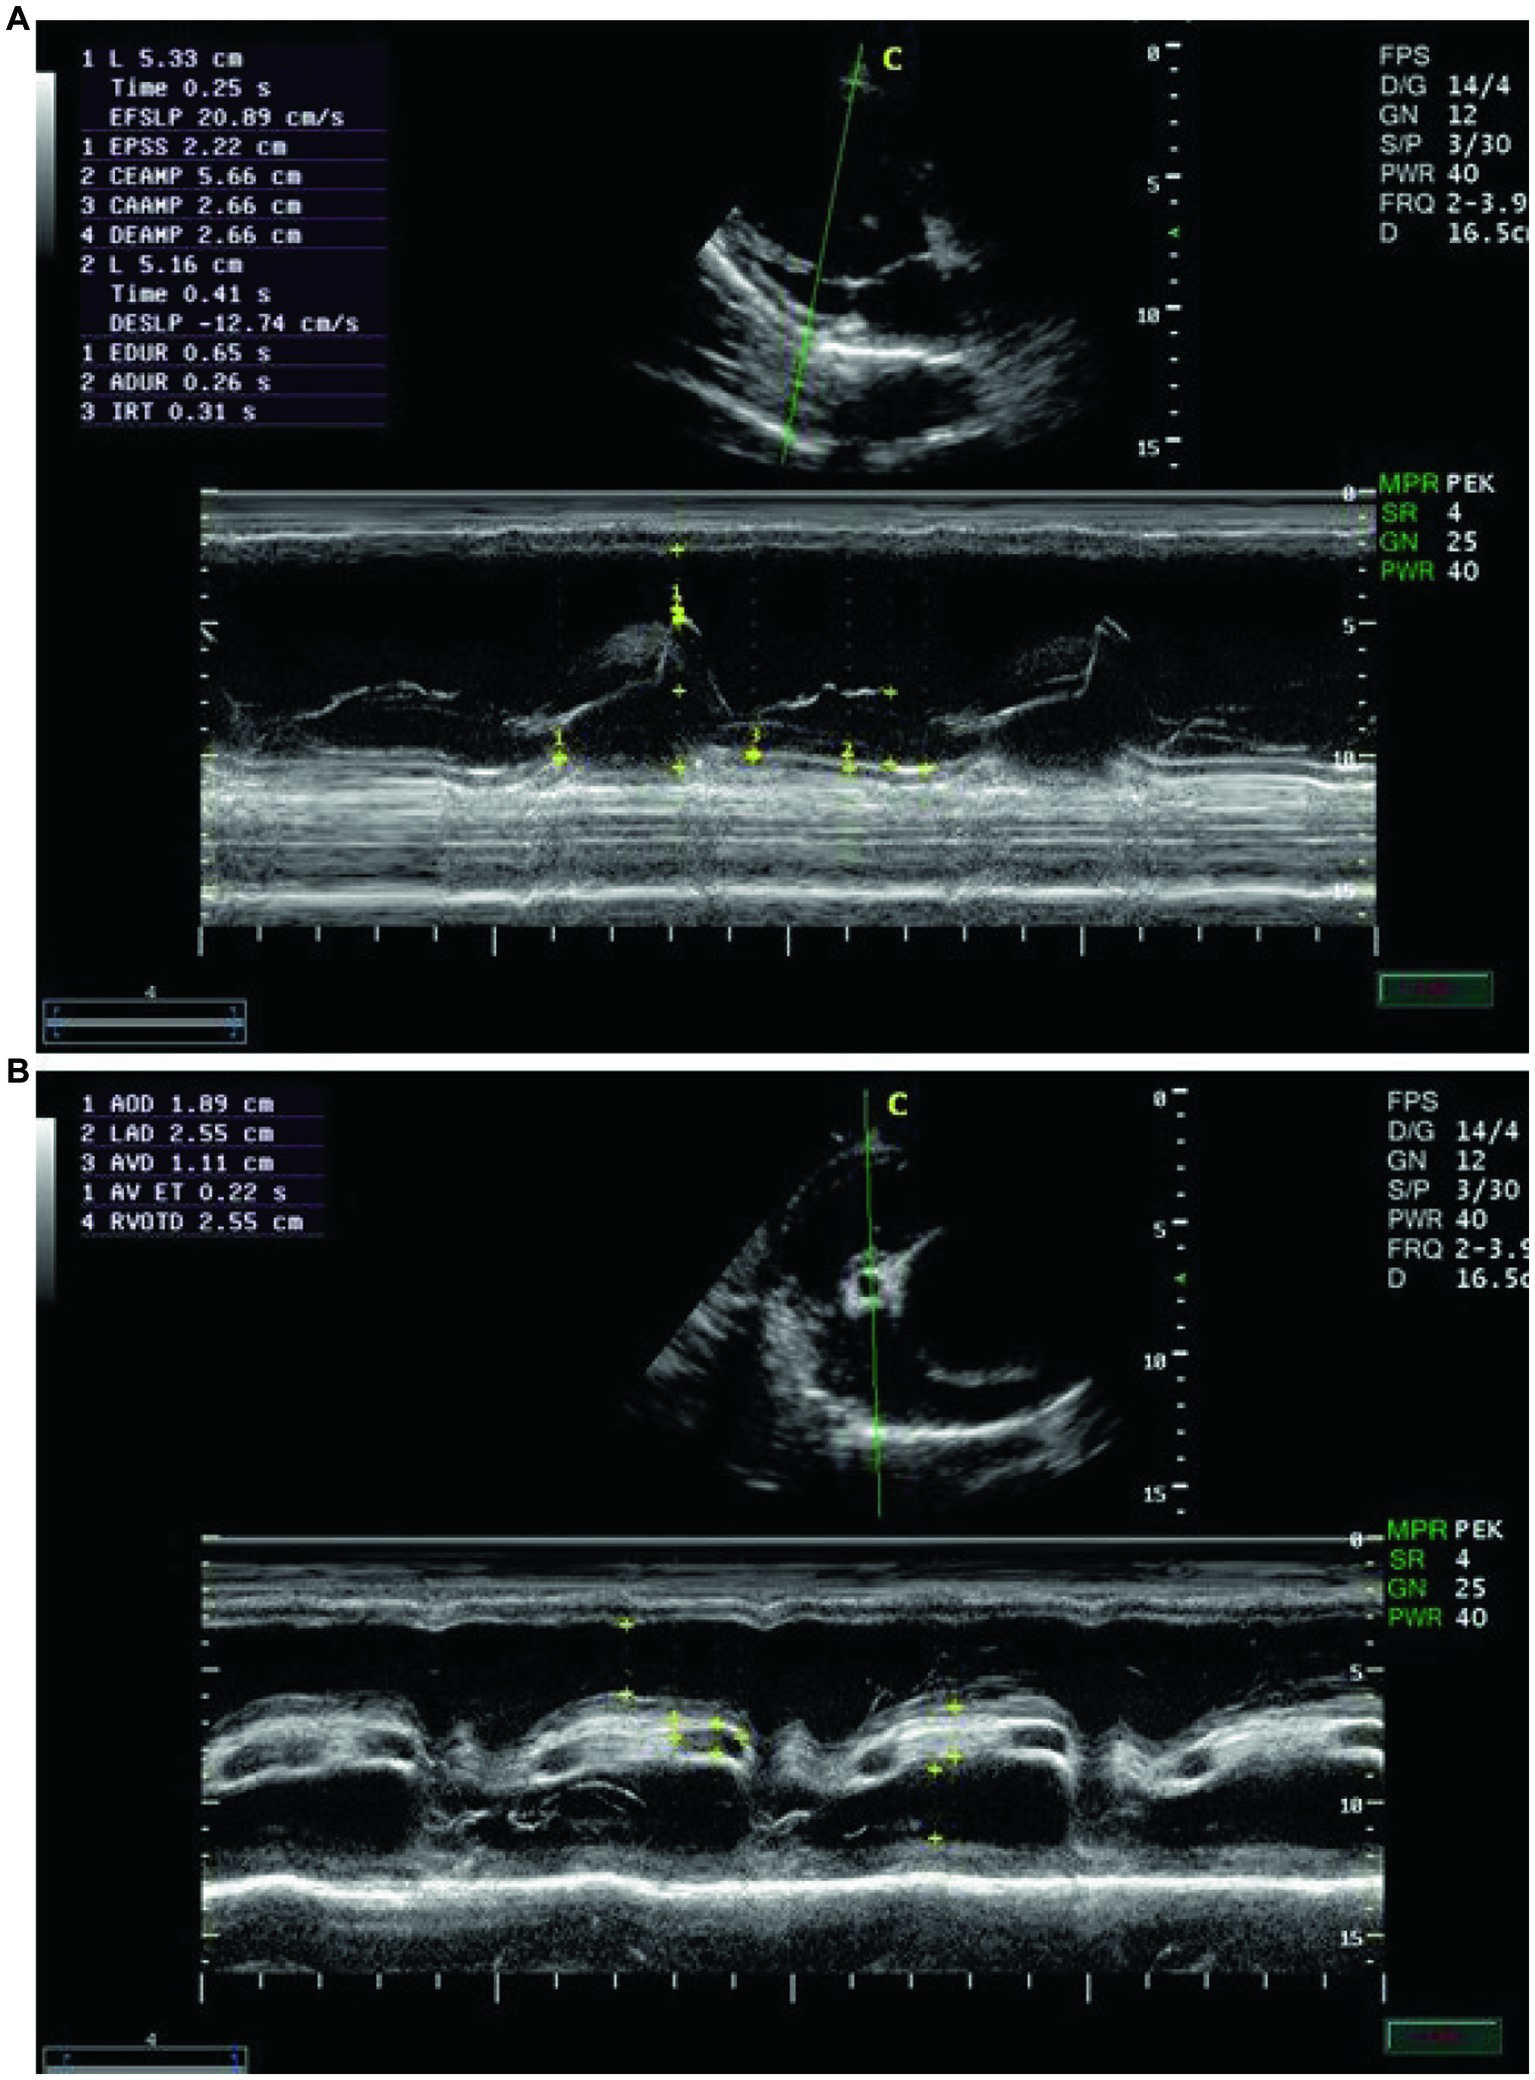

Echocardiographic findings were recorded to assess the left ventricular images (Figures 1A,B), mitral valve (Figure 2A), and aortic valve (Figure 2B) images in the examined donkeys. The effects of time, treatment, and time x treatment interaction after administration of metoclopramide and ondansetron in the investigated donkeys are presented in Tables 1–5. In general, FS% was significantly affected by the time for metoclopramide (p = 0.031) and ondansetron (p = 0.047) compared with placebo. However, treatment with metoclopramide provoked significantly higher percentages of FS at T60 (p = 0.009) and T90 (p = 0.028) compared with those of ondansetron and placebo. The time x treatment interaction also showed statistically significant alterations of FS% (p < 0.05), while values returned to the basal line at T240 (Table 1). Other cardiac dimensions, namely IVS, LVID, and LVPW at end-diastole and end-systole, EDV, ESV, and SV, and cardiac indices such as EF, showed no significant (p > 0.05) variation among the examined donkeys.

Figure 1

(A) The right parasternal long-axis view of the left ventricular outflow tract in examined donkeys using B-mode guidance for M-mode echocardiography. (B) The right parasternal view of the long-axis left ventricular outflow tract in examined donkeys using M-mode echocardiography at zero time. IVS = interventricular septum; LVID = left ventricular internal diameter; LVPW = left ventricular posterior wall.